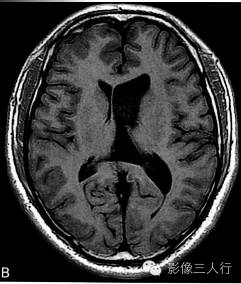

A.T2WI横断面;B.T1WI横断面;CFLAIR冠状面;D、E、F.增强横断面、矢状面、冠状面;G、H.CT平扫、增强;I.HE×100

肿瘤呈类圆形,边界清楚,位于左侧脑室前角及室间孔区,左侧脑室前角、三角部及左侧脑室后角扩张积水。MRI平扫T2WI(图A)肿瘤呈稍高信号,内见小范围高信号区;T1WI(图B)肿瘤呈等信号,内见低信号区;冠状面水抑制相(图C)肿瘤呈稍尚信号,内部原长T1长T2区信号呈低信号;增强扫描(图D~F)肿瘤强化不明显;CT平扫(图G)左侧脑室前角类圆形、边界清楚、较均匀等密度肿块,增强扫描(图H)强化不明显。